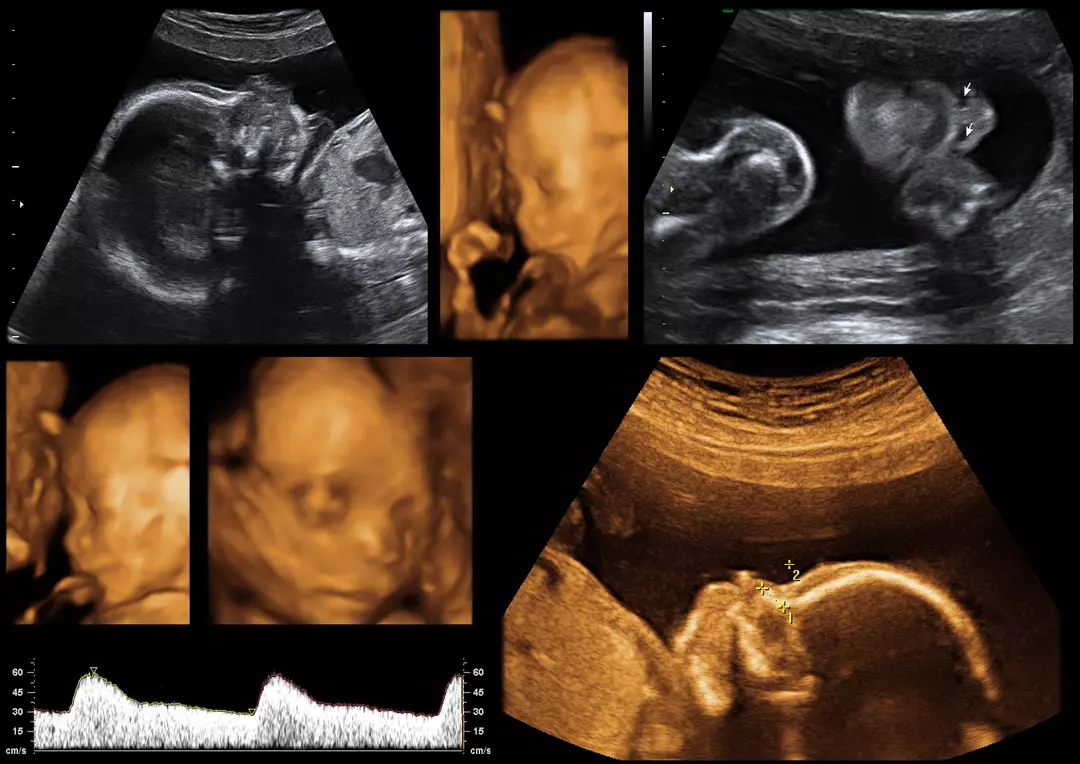

Dr. Boubker Idrissi, gynécologue-obstétricien et spécialiste en fertilité, accompagne ses patientes depuis plus de 20 ans à Tanger.

Une grossesse suivie sereinement, un accouchement en toute confiance.